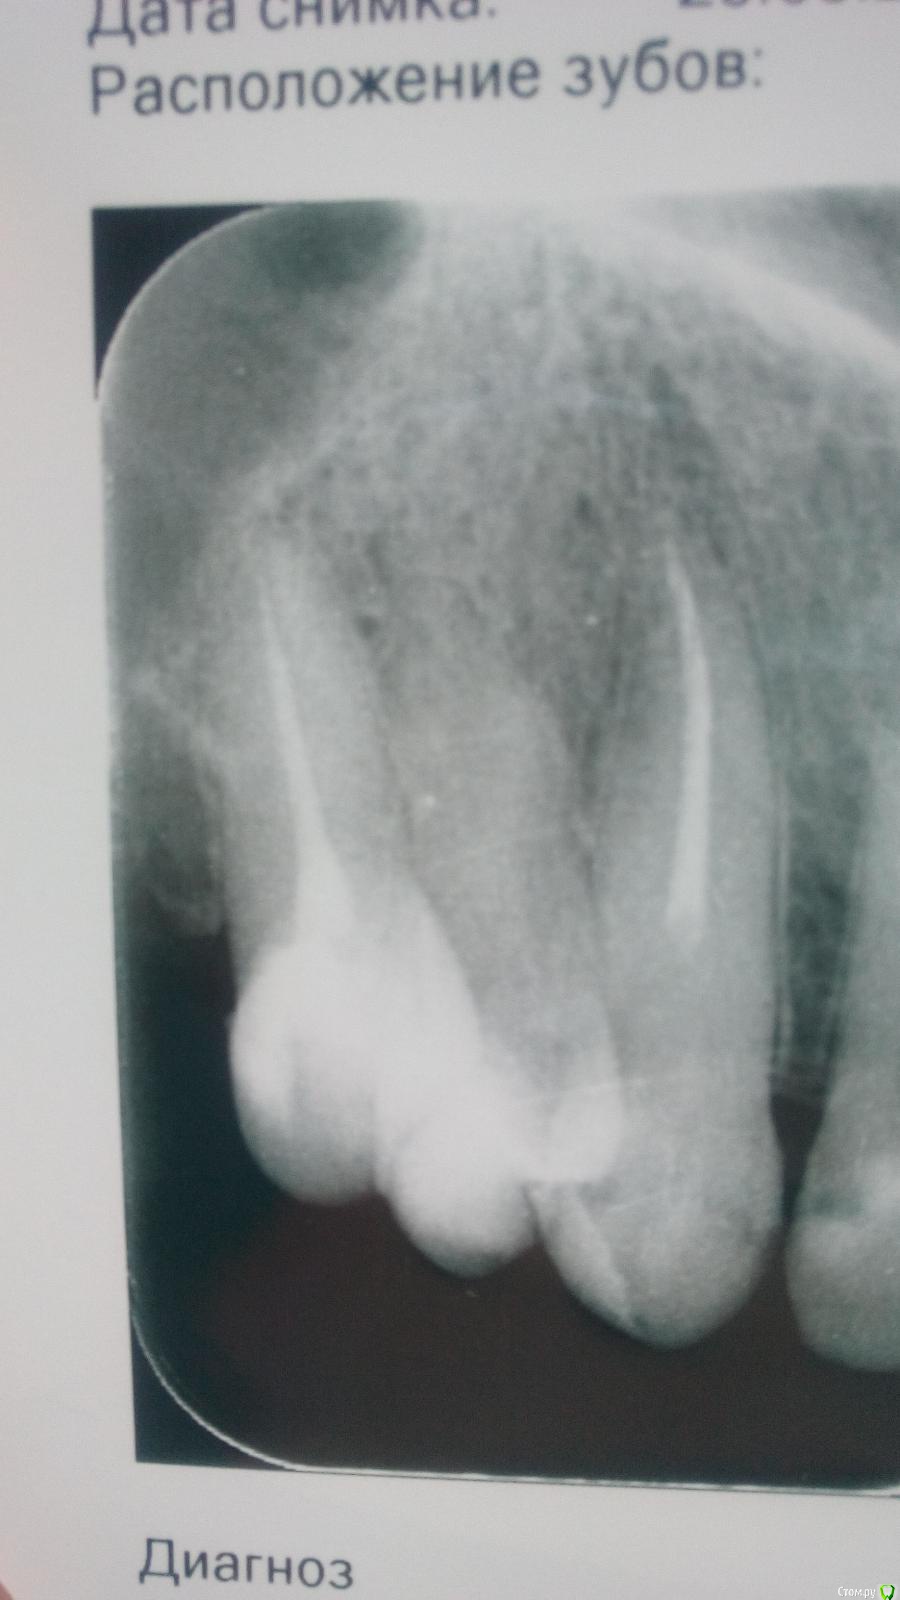

На7На Опубликовано 25 марта, 2018 Поделиться Опубликовано 25 марта, 2018 Здравствуете. Месяц назад была проведена операция цистэктомия, удаление 6, 7, 8 зубов. Киста была 28 мм х 23 мм. Перфорации не было как сказали, в пазуху не заходили. Киста ее прогибала. Зажило все хорошо. Швы сняли. Но больно нажимать на 5 зуб. Даже если языком сверху нажать больно. Не говоря уже что-то откусить. Сегодня сделала снимок. Зуб пролечен хорошо. Я не знаю что делать. Ссылка на комментарий

Irouil Опубликовано 25 марта, 2018 Поделиться Опубликовано 25 марта, 2018 (изменено) Все снимки в один день делали? Когда зуб подвергался лечению? Судя по первым, зуб нуждается в перелечивании. Чтобы говорить с максимальной уверенностью надо бы КТ сделать Изменено 25 марта, 2018 пользователем Irouil Ссылка на комментарий

На7На Опубликовано 25 марта, 2018 Автор Поделиться Опубликовано 25 марта, 2018 Все снимки в один день делали? Судя по первым, зуб нуждается в перелечивании. Чтобы говорить с максимальной уверенностью надо бы КТ сделатьДа снимки все сегодня. Перелечивать 5? Сегодня врач смотрел по снимку сказал хорошо пролечен, но он может давить на пазуху. Может поэтому боль? Ссылка на комментарий

Irouil Опубликовано 25 марта, 2018 Поделиться Опубликовано 25 марта, 2018 Да снимки все сегодня. Перелечивать 5? Сегодня врач смотрел по снимку сказал хорошо пролечен, но он может давить на пазуху. Может поэтому боль?Может, но месяц боли после операции - долговато. Реабилитация там должна была уже пройти. К сожалению плоскостные снимки обладают ограниченной информативностью. В такой ситуации как у Вас их можно интерпретировать двояко: не будь у Вас жалоб на боли, я бы тоже сказал, что наверное все хорошо. Я, все же, рекомендую 3д КЛ КТ. Верхнюю челюсть и верхнечелюстные пазухи, 12х8.5 хватит. Ссылка на комментарий